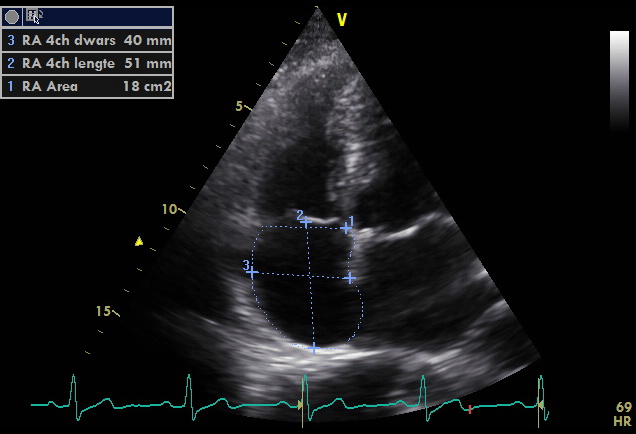

Right Atrial Enlargement ECG Stampede

Ekg Labeled And Explained Vrogue co